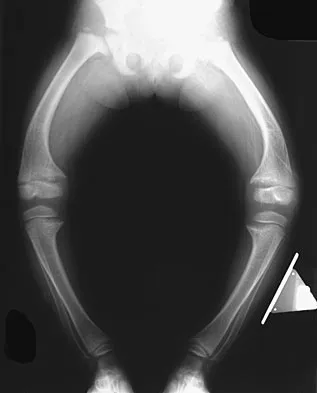

A 19-year-old man has had pain and swelling in his left forearm for the past 8 months. Laboratory studies show a mildly elevated WBC count and erythrocyte sedimentation rate. Radiographs are shown in Figures 58a and 58b, a CT scan is shown in Figure 58c, and T1- and T2-weighted MRI scans are shown in Figures 58d and 58e, respectively. A biopsy specimen is shown in Figure 58f. Immunohistochemistry demonstrates that the lesion is negative for leukocyte common antigen (CD34). What is the most common cytogenetic translocation associated with this lesion?

Explanation

The imaging studies show a permeative lytic destructive lesion in the proximal radius with "hair-on-end" periosteal reaction and a large soft-tissue mass most consistent with Ewing's sarcoma. The pathology reveals monotonous sheets of "round blue" cells. This limits the differential diagnosis to primary lymphoma of bone versus Ewing's sarcoma. These are best differentiated by immunohistochemistry, cytogenetics, and flow cytometry. Lymphoma of bone is typically CD34 positive and CD99 negative; whereas, the reverse is true of Ewing's sarcoma, CD34 negative and CD99 positive. The most common cytogenetic translocation with Ewing's sarcoma is 11; 22; 21; 22 and 7; 22 translocations have also been reported in Ewing's sarcomas. The X; 18 translocation is most commonly associated with synovial cell sarcomas; the 12; 22 translocation is most commonly associated with clear cell sarcomas; the 2; 13 translocation is most commonly associated with alveolar rhabdomyosarcomas, and the 12; 16 translocation is most commonly associated with myxoid liposarcomas. Flow cytometry is used to characterize the cell types of lymphomas. Womer R: The cellular biology of bone tumors. Clin Orthop Relat Res 1991;262:12-21. Yamaguchi U, Hasegawa T, Morimoto Y, et al: A practical approach to the clinical diagnosis of Ewing's sarcoma/primitive neuroectodermal tumour and other small round cell tumours sharing EWS rearrangement using new fluorescence in situ hybridisation probes for EWSR1 on formalin fixed, paraffin wax embedded tissue. J Clin Pathol 2005;58:1051-1056.